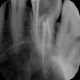

Rentgenowskie zdjęcie będzie także potrzebne czy wręcz niezbędne podczas przygotowań do leczenia kanałowego. Dzięki zdjęciu RTG lekarz będzie w stanie prawidłowo ocenić różne parametry zęba takie jak długość korzenia czy ilość kanałów.

Nasze przykładowe realizacje :